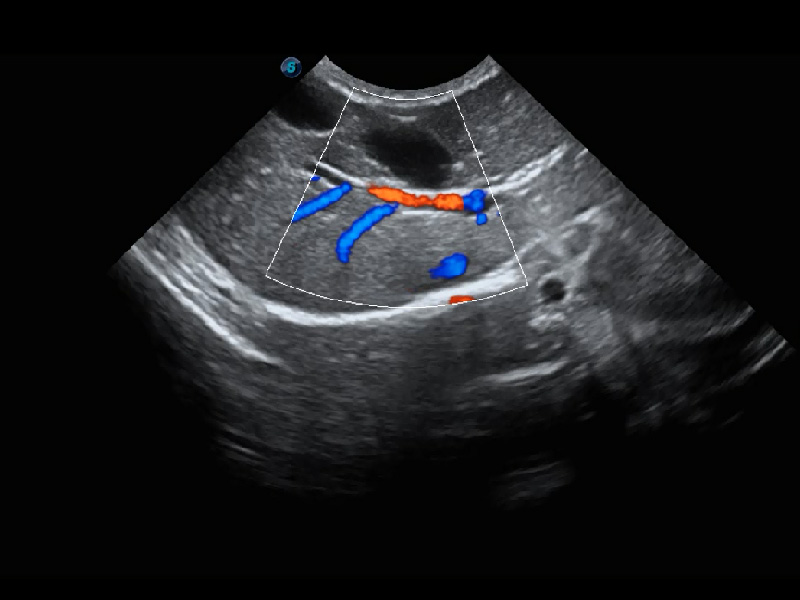

ProPet 60 作為一款高端臺式動物超聲設備,為動物醫(yī)生的日常診斷提供了一系列貼合動物臨床需求、解決臨床實際問題的高級成像功能。憑借全系列高清探頭,滿足醫(yī)生對腹部、心臟、生殖、淺表、肌骨等成像的所有需求,切實幫助您提升檢查效率,提高診斷信心。

動物是人類最親密的朋友和最值得信賴的伙伴。開立醫(yī)療也一直致力于探索動物專用的超聲影像解決方案。 全新推出的ProPet系列,是開立在動物超聲影像智能化、專業(yè)化、精準化的一次跨越式革新。動物不能用言語來表述自己的不適,通過超聲影像,ProPet系列搭建了動物醫(yī)生與不同物種溝通的“橋梁”,為動物醫(yī)生注入了“治愈之力”。